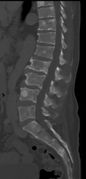

Pathological fracture of the lumbar spine due to multiple myeloma

CT scan of the lower vertebral column in a man with multiple myeloma, showing multiple osteoblastic lesions. These are more radiodense (brighter in this image) than the surrounding cancellous bone, in contrast to osteolytic lesions which are less radiodense.